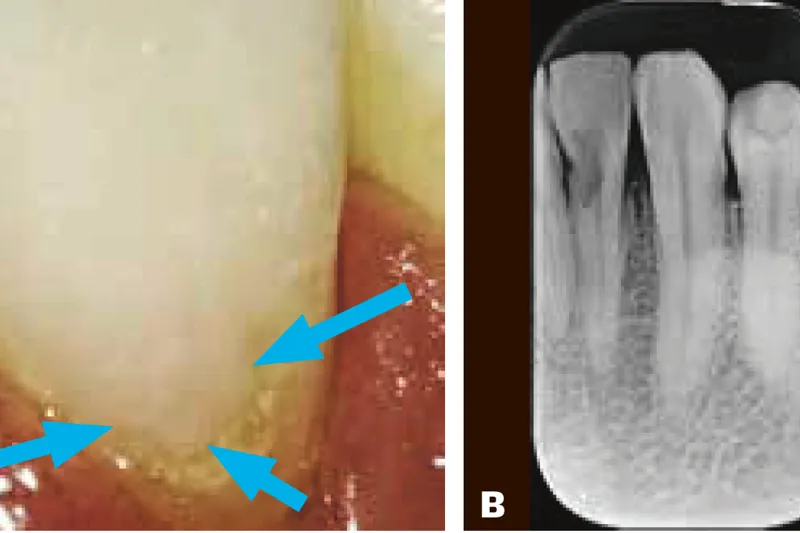

Klinisk kan både cervikal og intern resorption manifestere sig med et lyserødt gennemskin i kronen, og begge typer kan reagere positivt på vitalitetstest. Behandlingen af disse resorptionstyper er meget forskellig; det er derfor afgørende at stille den korrekte diagnose. Desuden er tidlig diagnostik vigtigt for tandens prognose. Røntgenundersøgelsen er et nødvendigt diagnostisk hjælpemiddel, og CBCT vil ofte være indiceret for at kunne diagnosticere typen, vurdere resorptionens udbredelse, træffe behandlingsvalg og planlægge behandlingen. Den primære behandling af en intern resorption vil være endodonti, mens den primære behandling af en ekstern resorption vil være fokuseret på fjernelse af resorptionsvævet og aflukning af resorptionskavitetens overfladebrud. Dette gøres eksternt fra, men i mere omfattende tilfælde vil en samtidig endodontisk behandling være nødvendig for at fjerne alt resorptionsvævet.

Særligt kan det være vanskeligt at skelne mellem intern og cervikal resorption (hvis overfladebruddet er meget lille), og det vurderes, at CBCT er et væsentligt supplement til den initiale 2-d-røntgenoptagelse for at opnå den korrekte diagnose, samtidig med at metoden bidrager med information, der er essentiel for vurdering af behandlingsmuligheder. Nærværende artikel giver et generelt overblik over den kliniske og radiologiske diagnostik af resorptioner.